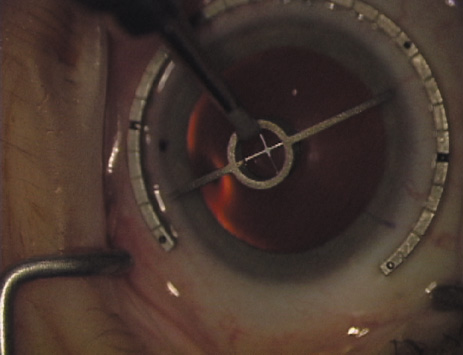

ways. Our preferred method makes use of a modified Fine-Thornton fixation

ring (Nichamin Fixation Ring and Gauge; Mastel Precision, Storz, Rhein

Medical). This instrument serves to fixate and position

the globe in order to optimize incision placement, as well as to delineate

the extent of arc to be incised. One visually extrapolates from

the limbus to marks on the surface of the ring. Each incremental mark

is 10 degrees apart, and bold hash marks (180 degrees) opposite

to each other serve to align and center the incision over the steep

meridian. This approach obviates the need to ink and physically mark

the cornea. If one desires, particularly when first gaining experience

with LRIs, a two-cut RK marker may be used to place ink marks upon the

cornea to show the exact extent of arc that is to be incised, in conjunction

with the fixation ring/gauge (Fig. 4). Alternatively, various press-on markers are available, such as

markers, rings, and blades for performing LRIs.  Fig. 4. The Nichamin Fixation Ring and Gauge serves to both fixate the globe and

delineate the extent of arc to be incised; a two-cut radial marker may

be used to mark the extent of arc to be incised, and the Mastel Nichamin

Force AK Diamond Blade with preset depth of 600 microns. Fig. 4. The Nichamin Fixation Ring and Gauge serves to both fixate the globe and

delineate the extent of arc to be incised; a two-cut radial marker may

be used to mark the extent of arc to be incised, and the Mastel Nichamin

Force AK Diamond Blade with preset depth of 600 microns.